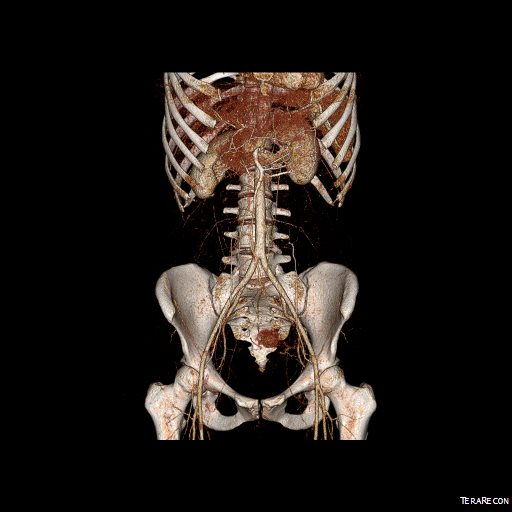

Examination was remarkable for a well nourished young woman in distress with epigastric tenderness. Inflammatory markers were normal and she was on methotrexate and tocilizumab. CTA (above) and duplex showed severe stenoses affecting the origins of the celiac axis and superior mesenteric artery. A composite of the centerlines through these showed the arteries to be critically narrowed at their origins (below), along with a mild to moderate stenosis of the aorta (above). No active inflammation could be seen.

The anterior view of the 3DVR images of her CT showed an absence of collateralization via the inferior mesenteric artery and Arc of Riolan.